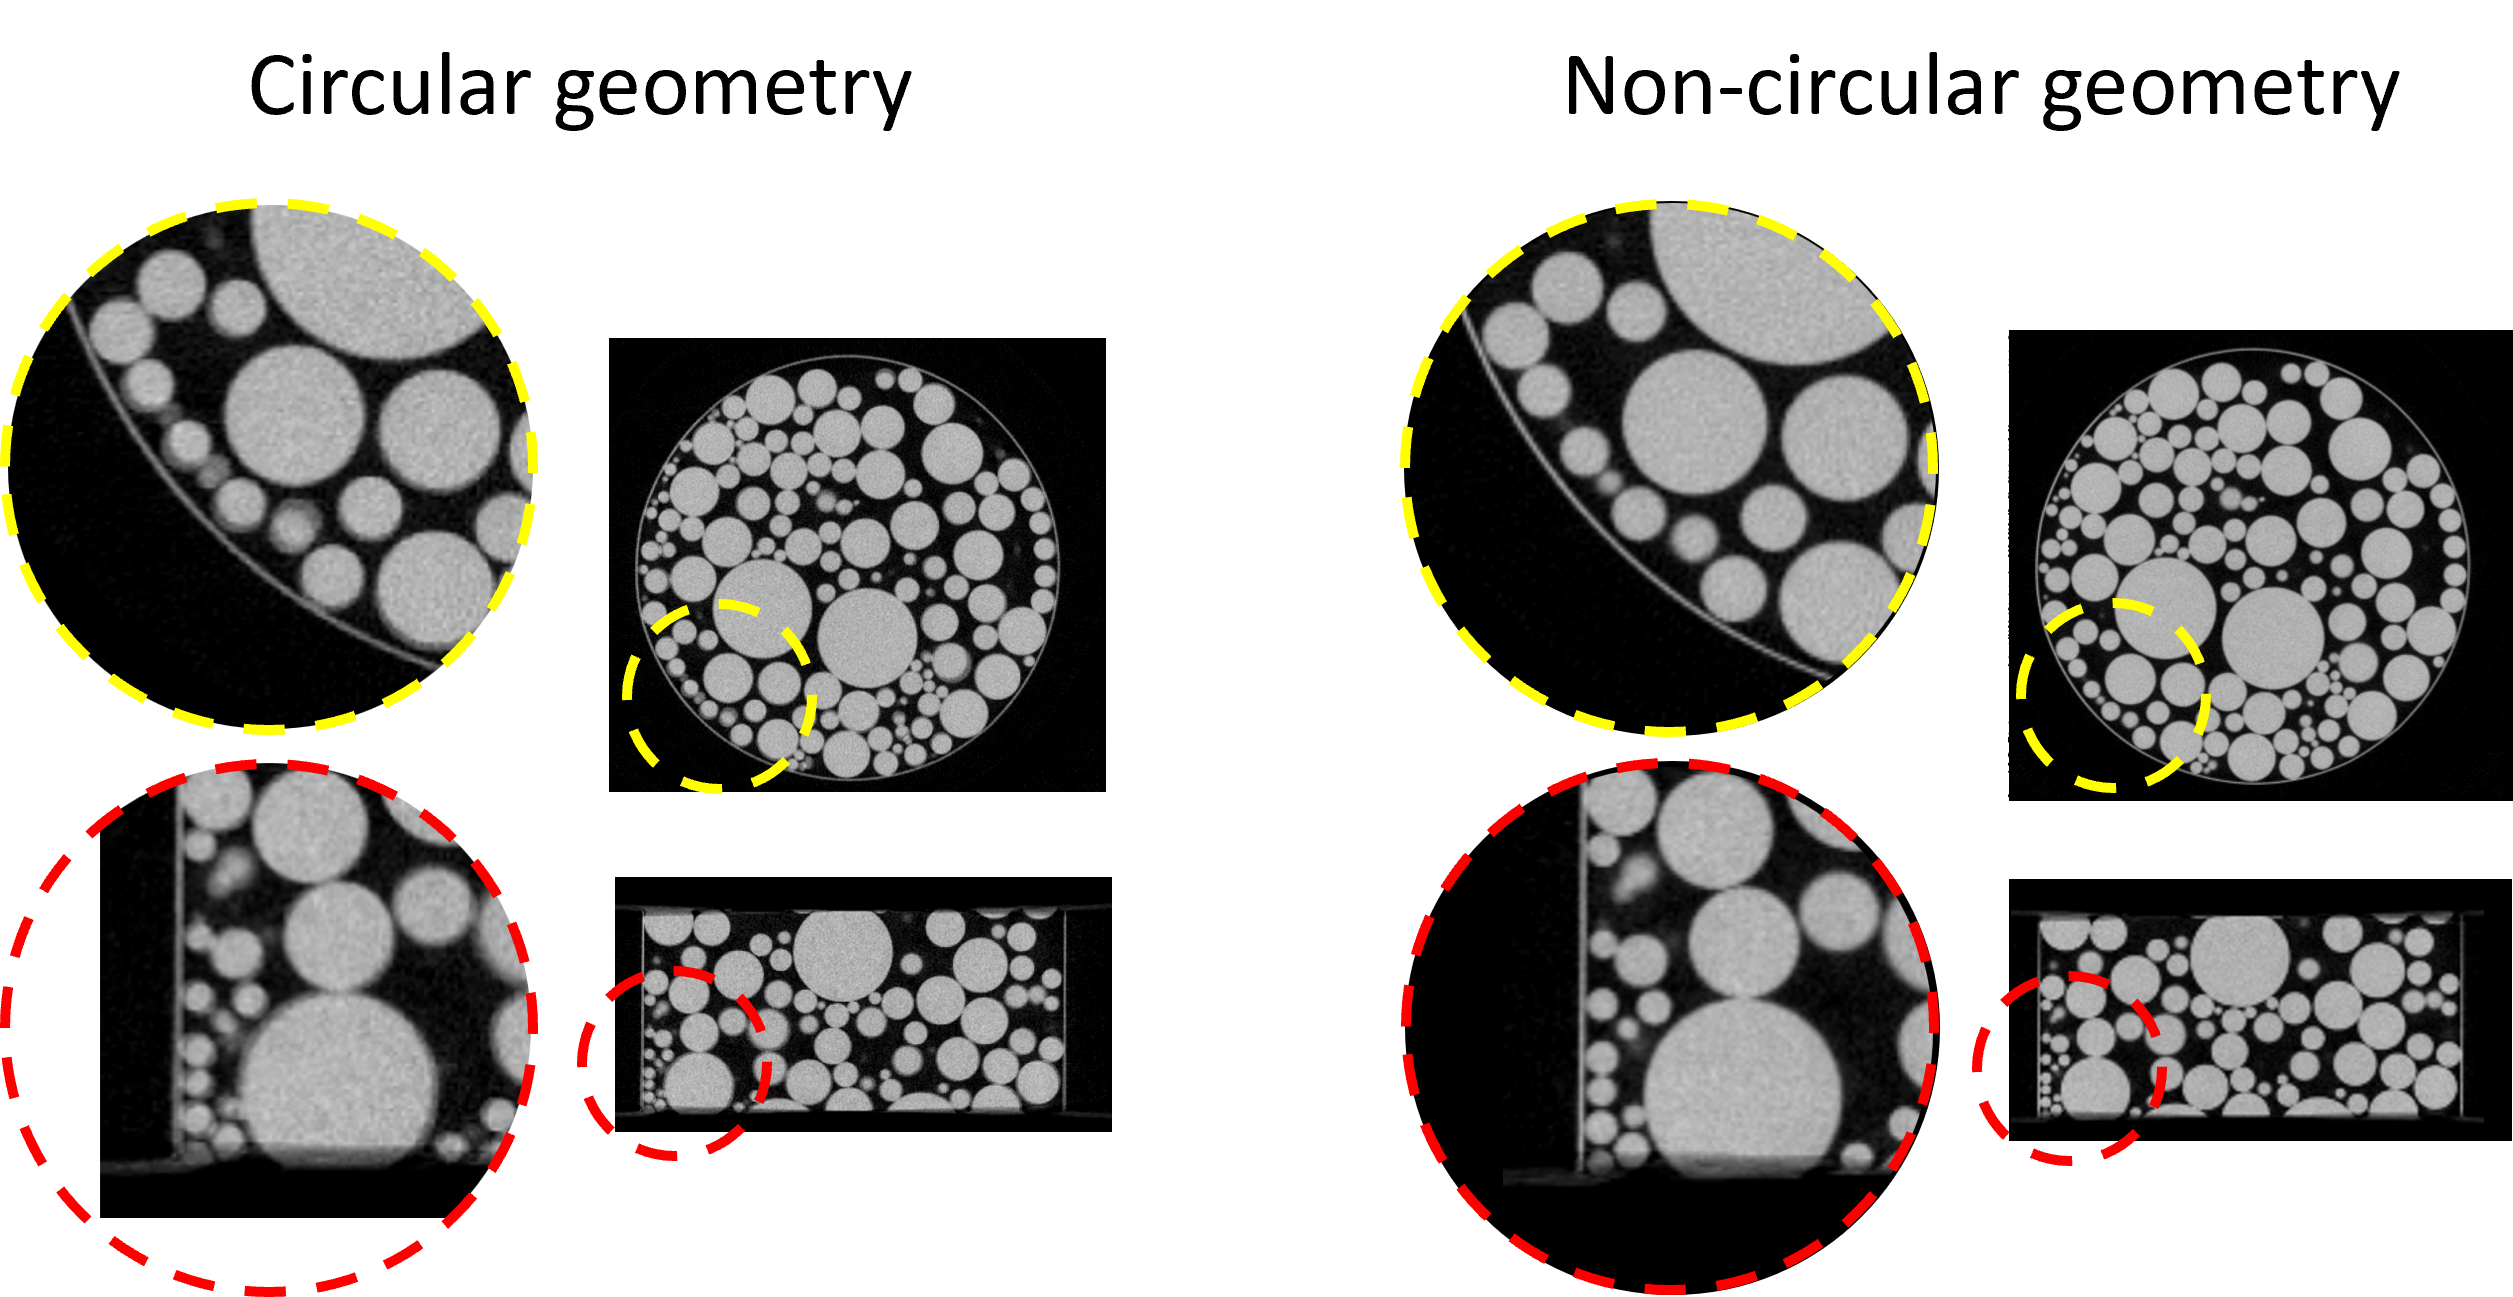

Figure 5: FBP reconstruction using the bottom-layer projections from a dual-layer CBCT system using different geometry definition. The non-circular geometry add a 0.4°0.4\degree in-plane rotation, effectively mitigating the edge blurring in the recon with circular geometry.

We validated the CTorch projector for both circular and non-circular geometries using physical x-ray bench data. A plastic ball phantom was scanned on a laboratory benchtop CBCT system equipped with a dual-layer flat-panel detector[22]. The two-layer projections were reconstructed separately using the FBP algorithm under a 3D circular geometry assumption. Fig. 5 presents the reconstruction results for the top layer using different projectors. Each projector accurately depicts the ball shape with sharp edges, demonstrating the high geometric accuracy of the CTorch circular-scan projector. Fig. 5 shows the bottom-layer results. When the projections are backprojected under the circular geometry assumption, geometric distortions are noticeable, particularly around the ball edges. These distortions may arise from misalignment of the detector pixel grids between the two layers. However, by shifting to a non-circular geometry model that incorporates a 0.4°0.4\degree in-plane detector rotation, the distortions are substantially reduced. This validates the accuracy of the CTorch non-circular projector and highlights the importance of flexible geometry descriptions for processing nonideal physical projection data.